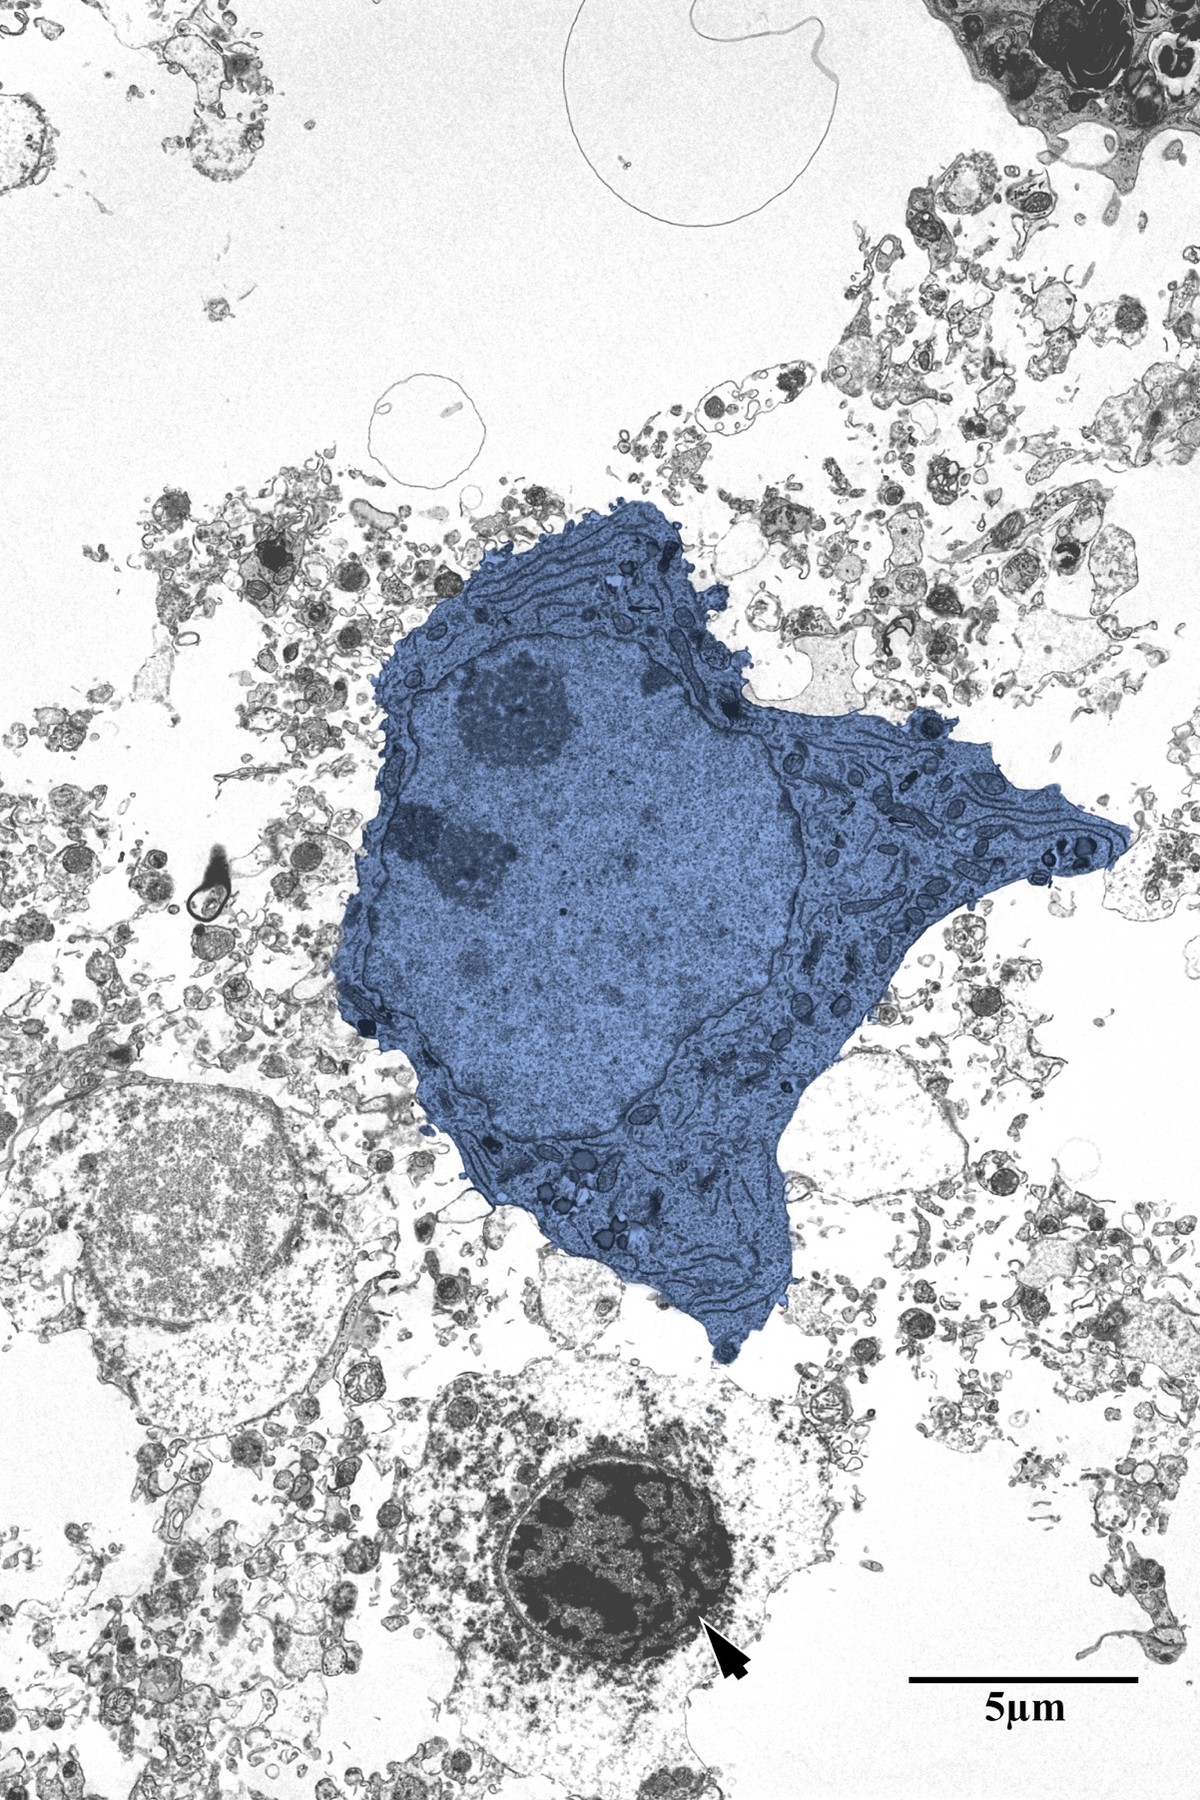

Necrotic Core & Infarct Zone

Within the necrotic core, neurons show complete loss of organellar integrity — barren dendritic processes, no identifiable synapses, and pyknotic glial cell nuclei. This zone is characterized by widespread degenerating neuropil tissue and the complete absence of functional synaptic structures.

Degenerating neuron and pyknotic glial cell in the necrotic core

Necrotic core: degenerating neuron (blue) and pyknotic glial cell (arrow) surrounded by disintegrating neuropil. No identifiable synapses were observed within this region. Scale bar: 5 µm. From Bayati, BSc Honours Thesis 2018.